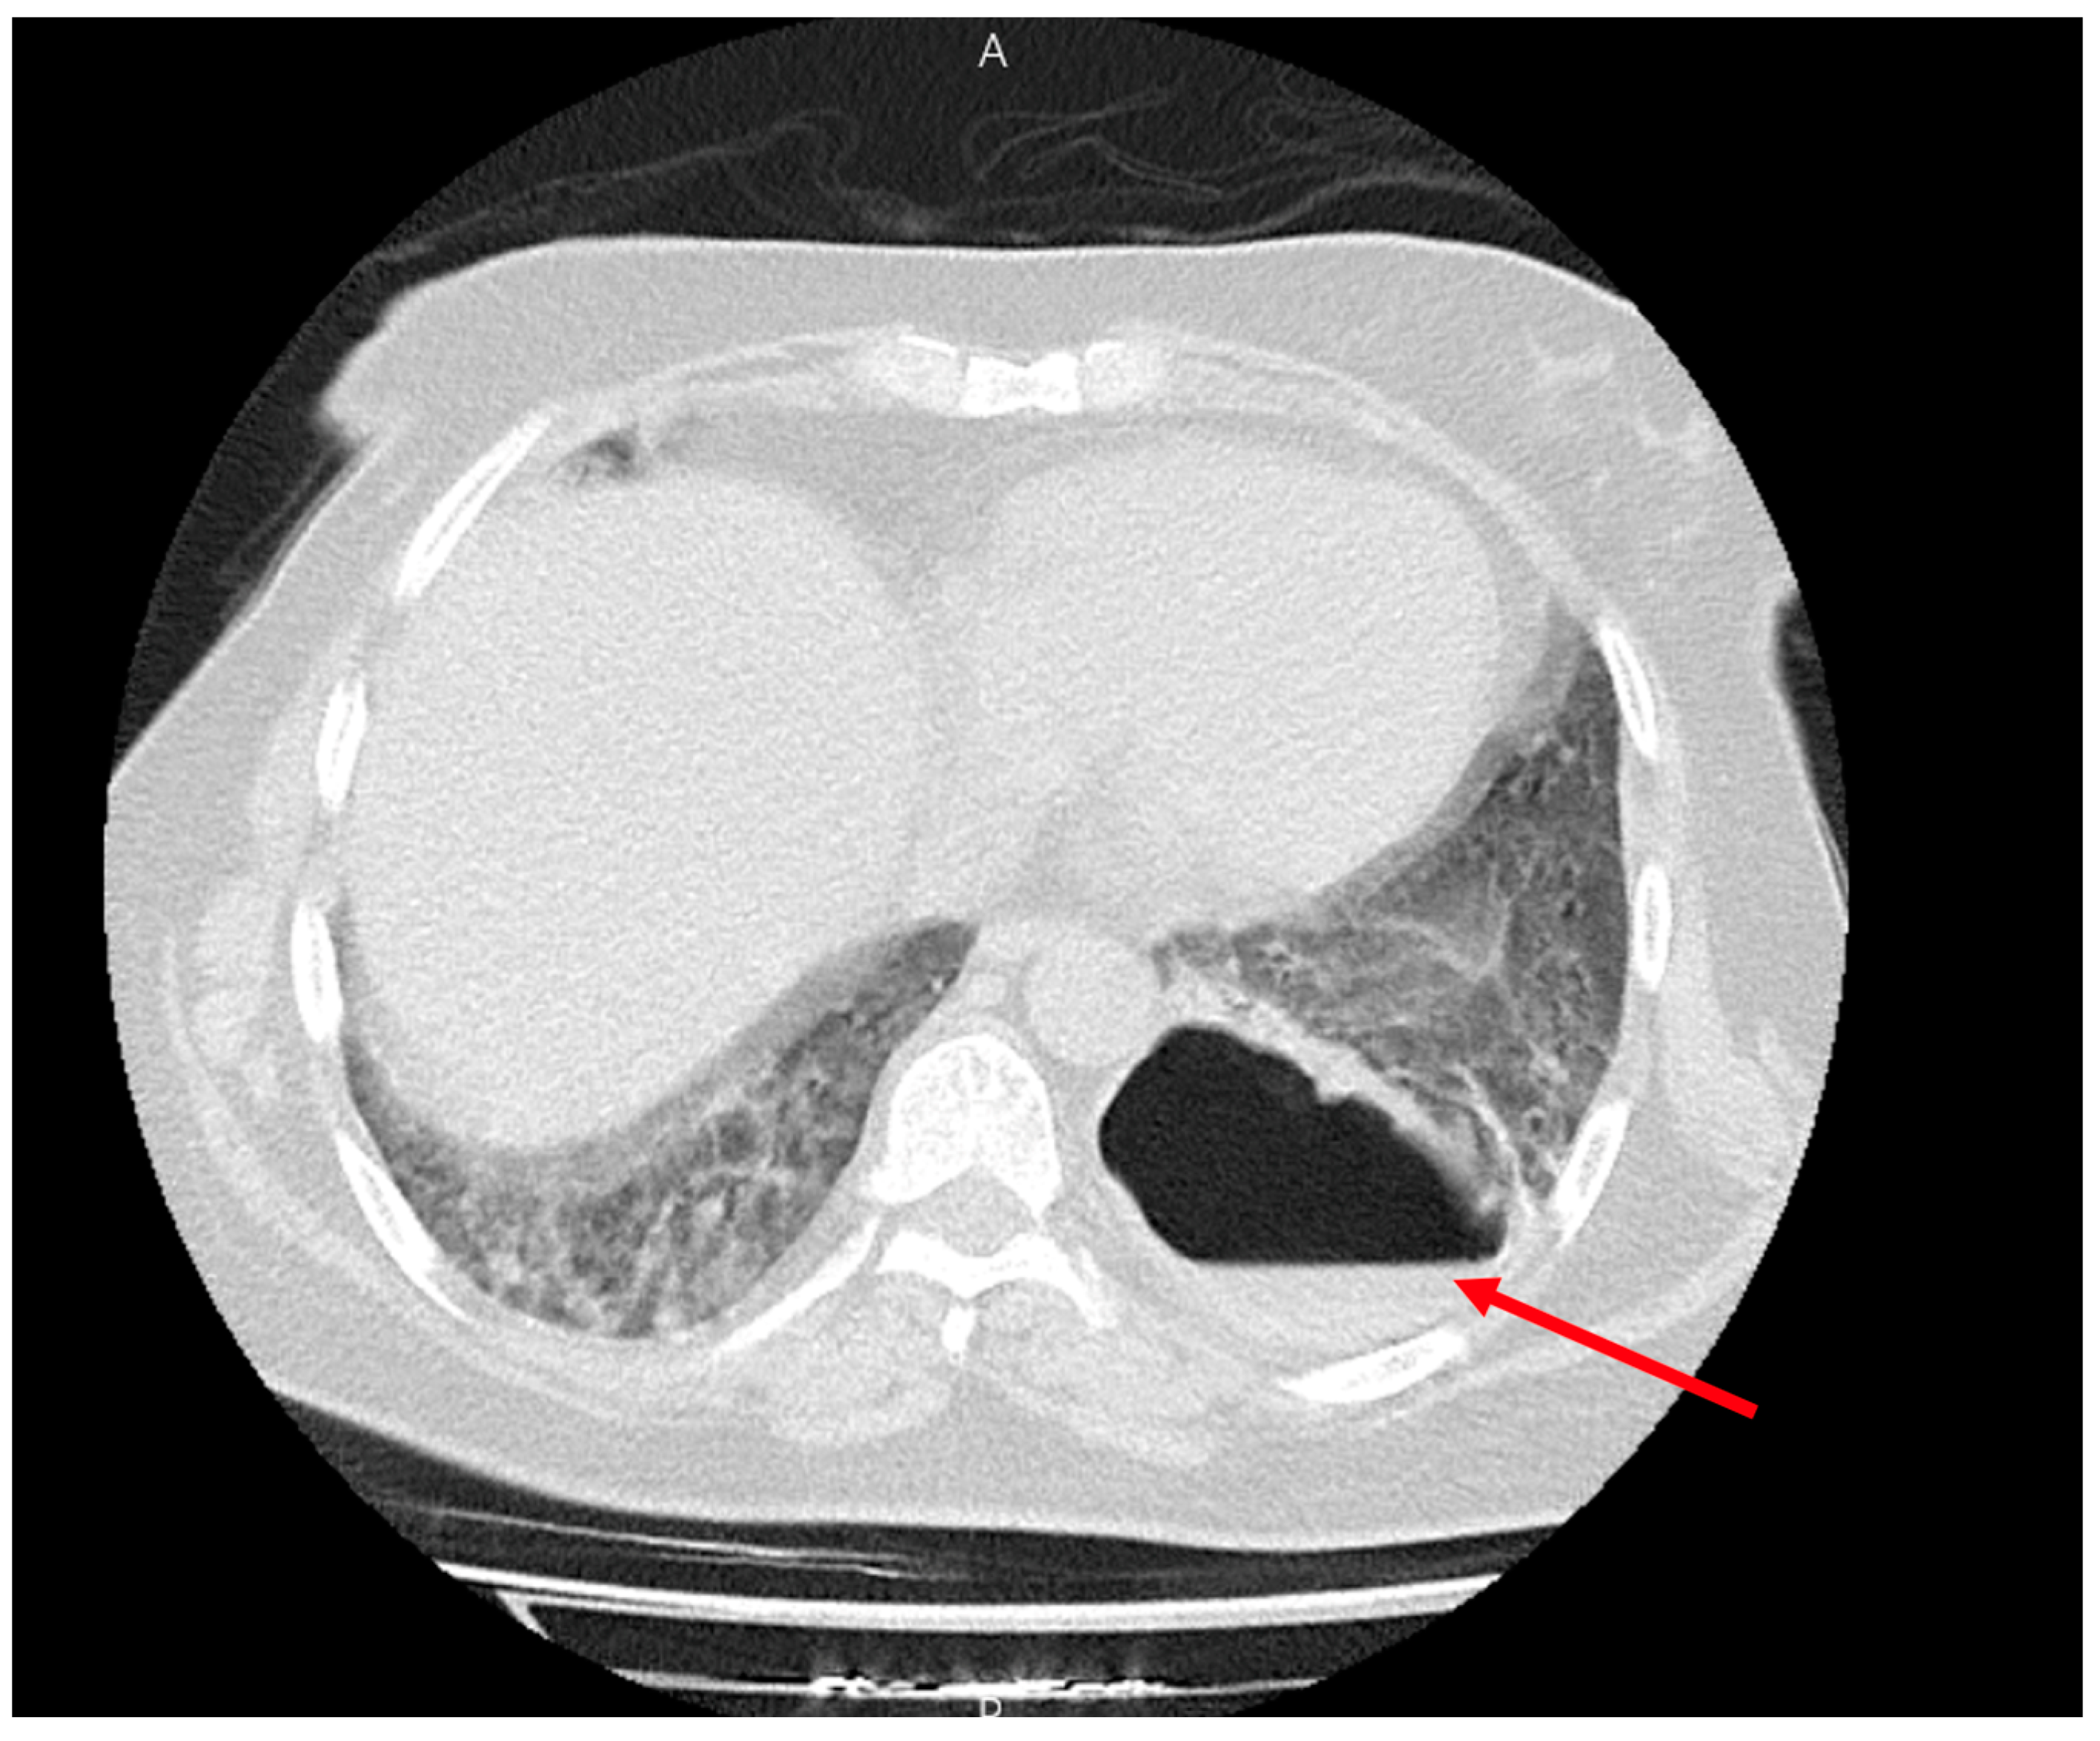

Figure 2.

Large cavity with the air-fluid level in the left lower lobe (red arrow).